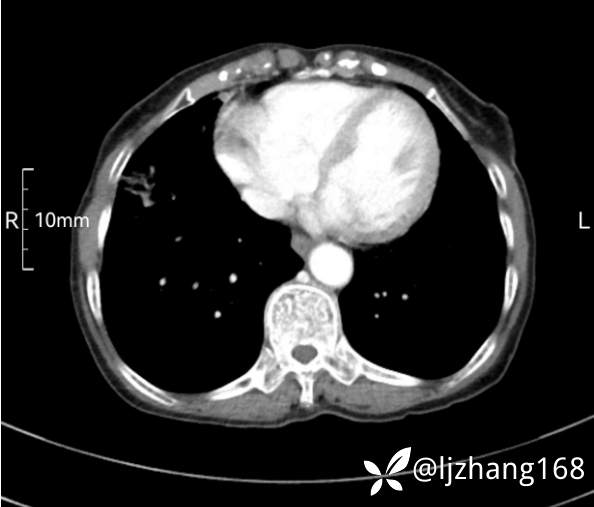

74岁女患,反复咳嗽2月,右肺空洞性病变,炎症OR肿瘤(有病理)

简要病史:2月前开始受凉后出现咳嗽,咳少许白色粘液痰,痰不易咳出,无痰中带血及咯血,无畏寒发热,外院胸部CT提示右下肺空洞病变,脓肿可能性大,常规抗感染治疗效果不佳。既往否认“糖尿病”等病史,有高血压基础病史,无吸烟史。

辅助检查:胸部CT右肺下叶前基底段结节并空洞

临床诊断:右肺空洞:脓肿?